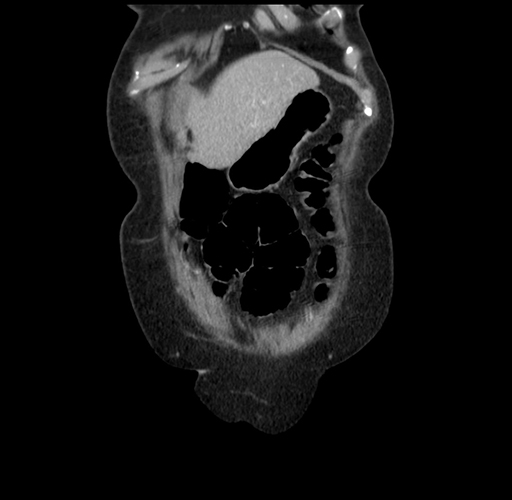

Pre-Chemo: Coronal Venous